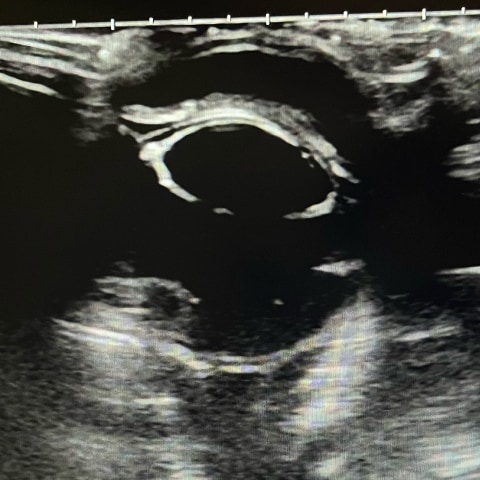

眼房内の出血があり眼圧測定にて高眼圧を確認しました。緊急的な点眼薬による眼圧降下治療を実施後、網膜剥離あり視覚回復せず、疼痛が継続していたため疼痛管理を目的とし強膜内シリコンインプラントを実施しました。

眼圧の上昇は目が腫れることで痛みや出血、視神経障害による失明を引き起こすことがあり早期発見、早期治療が大切です。目が腫れている、反対の目に比べて前に出てきている、目が赤い、目を痛がるなどの症状があればお早めにご相談くださいね。